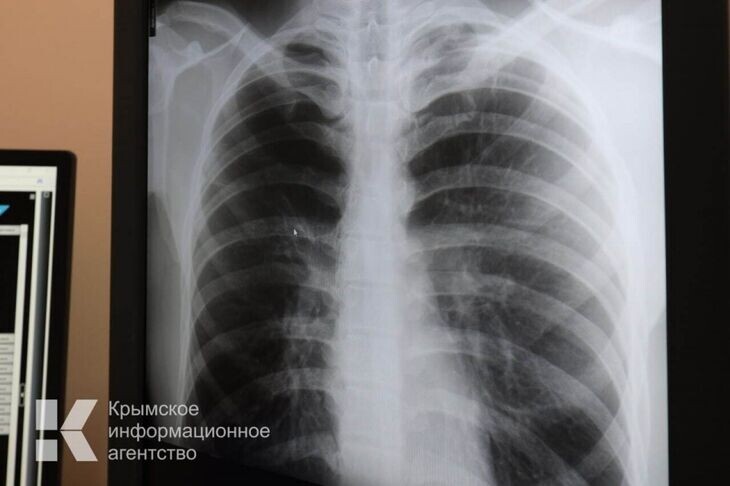

В Крыму за 12 лет заболеваемость туберкулёзом снизилась на 62%

Единственным способом выявить болезнь на ранних этапах развития являются ежегодные профилактические осмотры. Обследование проводится как в медорганизациях, так и в ходе выездных профмероприятий – в этих целях районные и городские больницы оснащены передвижными цифровыми флюорографами.

«Основным симптомом туберкулеза является длительный кашель. Если у человека появился кашель, который длится более трёх недель, необходимо обратиться к терапевту. Врач направит на исследование мокроты и рентгенологическое обследование», - отметила главный крымский фтизиатр.